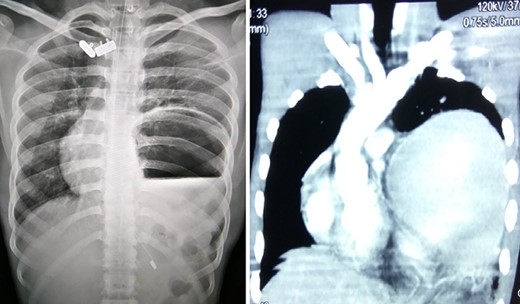

A 25-year-old-male presented to emergency department with 2 days of abdominal pain and non-bilious vomiting. His vitals were stable. The abdominal examination revealed epigastric fullness. There was no tenderness or organomegaly. The laboratory investigation showed normal hemoglobin (12.6 gm/dl), leukocytosis (18 200 cells/mm3) and normal renal function test and serum chemistry. Chest and abdominal X-ray showed elevated left hemi-diaphragm, grossly dilated and spherical stomach with large air-fluid level occupying whole of the upper abdomen (Fig. 4). The diagnosis of gastric volvulus was made and further confirmed by CT. Nasogastric decompression was attempted, but was futile. Patient was resuscitated, injectable broad-spectrum antibiotic commenced and planned emergency laparotomy. At surgery, organo-axial gastric volvulus was seen lying totally in the abdominal cavity, which was de-rotated and series of anterior abdominal wall suture gastropexy performed to prevent recurrently. The patient had an uneventful postoperative course. He was discharged on Day 7. At 28 months follow-up, the patient is asymptomatic.

X-ray showing a markedly distended and spherical stomach suggesting gastric volvulus.